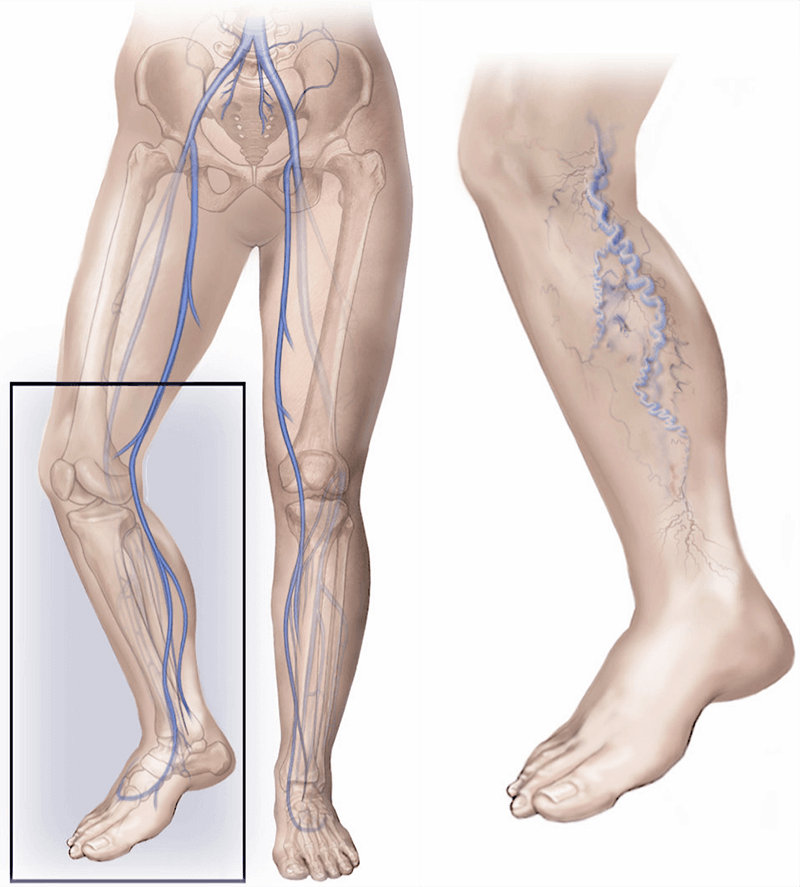

Varicose veins are veins that have become enlarged, stretched and tortuous, most commonly affecting the legs. They often appear raised, bluish or purplish, and may be visible just beneath the skin.

There are two main vein systems in each leg. The deep veins lie within the muscles and carry the majority of blood back towards the heart. The superficial veins sit closer to the surface of the skin. Varicose veins develop in these superficial veins.

When the vein walls or the small one-way valves inside the superficial veins become weak, blood does not flow efficiently upwards. This leads to increased pressure within the vein. Over time, the vein stretches and becomes swollen and twisted, forming a varicose vein.